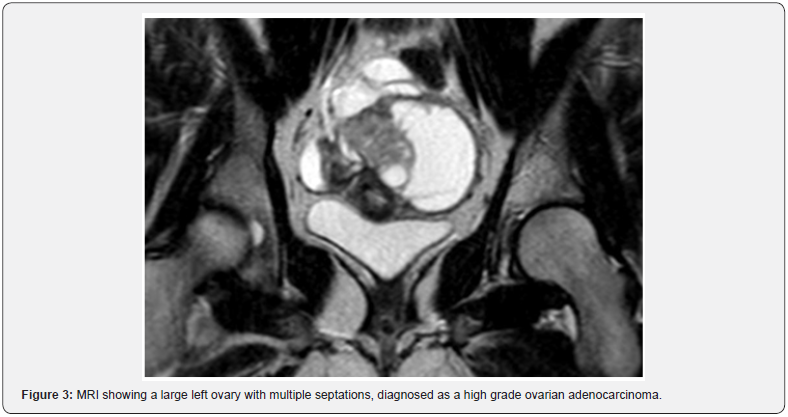

Over the next three years she had multiple new malignancies: Urothelial atypia detected on routine screening cystoscopy, glioblastoma multiforme (Figure 2) detected by brain MRI, endometrial adenocarcinoma after developing menorrhagia, high grade ovarian adenocarcinoma after an episode of lower abdominal pain, and recurrent adenocarcinoma of the colon found on screening colonoscopy. KP has undergone medical and surgical management including intravesical mitomycin, craniotomy with tumor resection, radiation and chemotherapy, and multiple colectomies with revisions (Figure 3).

One of KP’s life goals was to maintain fertility in order to carry out a pregnancy and become a mother. After her diagnosis of endometrial adenocarcinoma, she refused a total abdominal hysterectomy with bilateral salpingo-oophorectomy knowing that her chances of developing further malignancies was almost guaranteed. She eventually accepted the procedure after the cancer had metastasized to her ovaries and was optimistic about the possibility of future adoption.